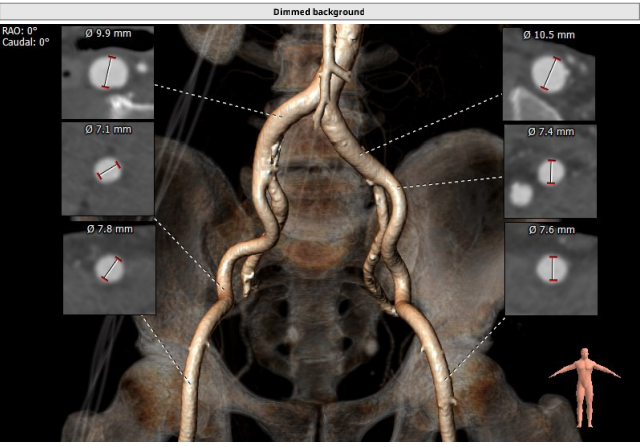

术前CT测量:

瓣环:27mm;LVOT:26.8mm;STJ:37.9mm;升主动脉:37.4mm;左冠高度:20.2mm;右冠高度:28.9mm;钙化积分:18mm3;瓣环与水平面夹角:29°;心尖入路夹角:108°。

计算机三维重建: